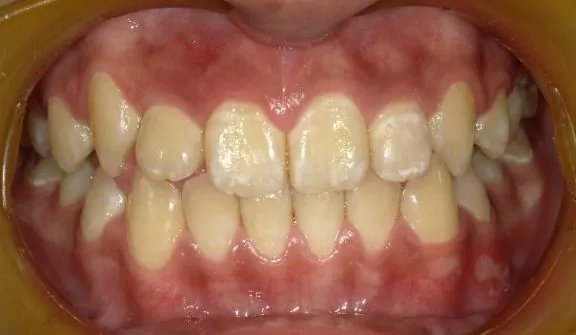

治療後

口腔衛生指導後、マウスピース型矯正歯科装置にて歯の移動を行いました。右上の犬歯の生えるスペースがありませんでしたから、歯を移動することで排列スペースをつくっています。Ⅰ期治療が終了したところで、ご本人と保護者の方が満足されているため経過観察中です。すべての永久歯が萌出したところで、セカンドフェーズ(Ⅱ期治療)を行うか判断する予定です。

永久歯の抜歯なし